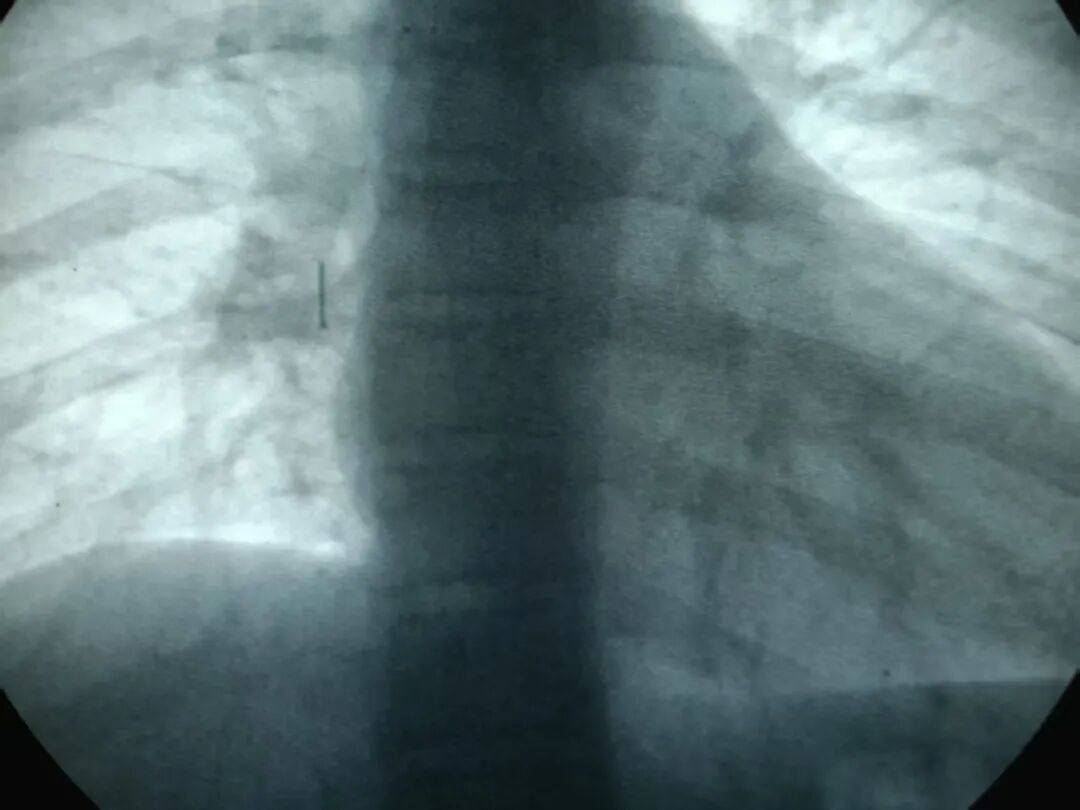

3月13日,家东说念主带他到当地病院作念了胸部CT,评释指示“右肺下叶实变影,支气管炎”。医师提议进一步查验,于是他们来到山东大学王人鲁第二病院北院区呼吸与危重症医学科就诊。

呼吸与危重症医学科副主任、呼吸介入亚专业主任王永彬仔细阅片、详备问诊,推敲孩子明确的异物吸入史,高度怀疑气管内异物。今日中午,团队立即为小刘进行急症支气管镜查验,因异物为图钉,极易形成气管内大出血,与麻醉科等多科室反复盘算推算,并进行内镜下推演术中可能遭逢的多样问题,并备好多样器材及一朝出现大出血的多样预案。

小刘气管插管后,气管镜进程隆突,刚探入右主支气管,屏幕上就出现了异样——遍及黄白色脓性分泌物附着在管壁,真是堵住了视线。王永彬小心操控镜子,一边眩惑一边推动,吸除分泌物后,一个被鲜红色肉芽组织紧紧包裹的异物迟缓显清爽来,正卡在右上叶支气管启齿处,犀利的针头依然深深镶嵌进周围组织中。